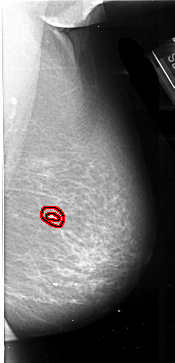

RIGHT_MLO LINES 6526 PIXELS_PER_LINE 3136 BITS_PER_PIXEL 16 RESOLUTION 42 OVERLAY

FILE: A_1009_1.RIGHT_MLO.OVERLAY

TOTAL_ABNORMALITIES 1

ABNORMALITY 1

LESION_TYPE MASS SHAPE IRREGULAR MARGINS SPICULATED

ASSESSMENT 4

SUBTLETY 1

PATHOLOGY MALIGNANT

TOTAL_OUTLINES 2

BOUNDARY

CORE